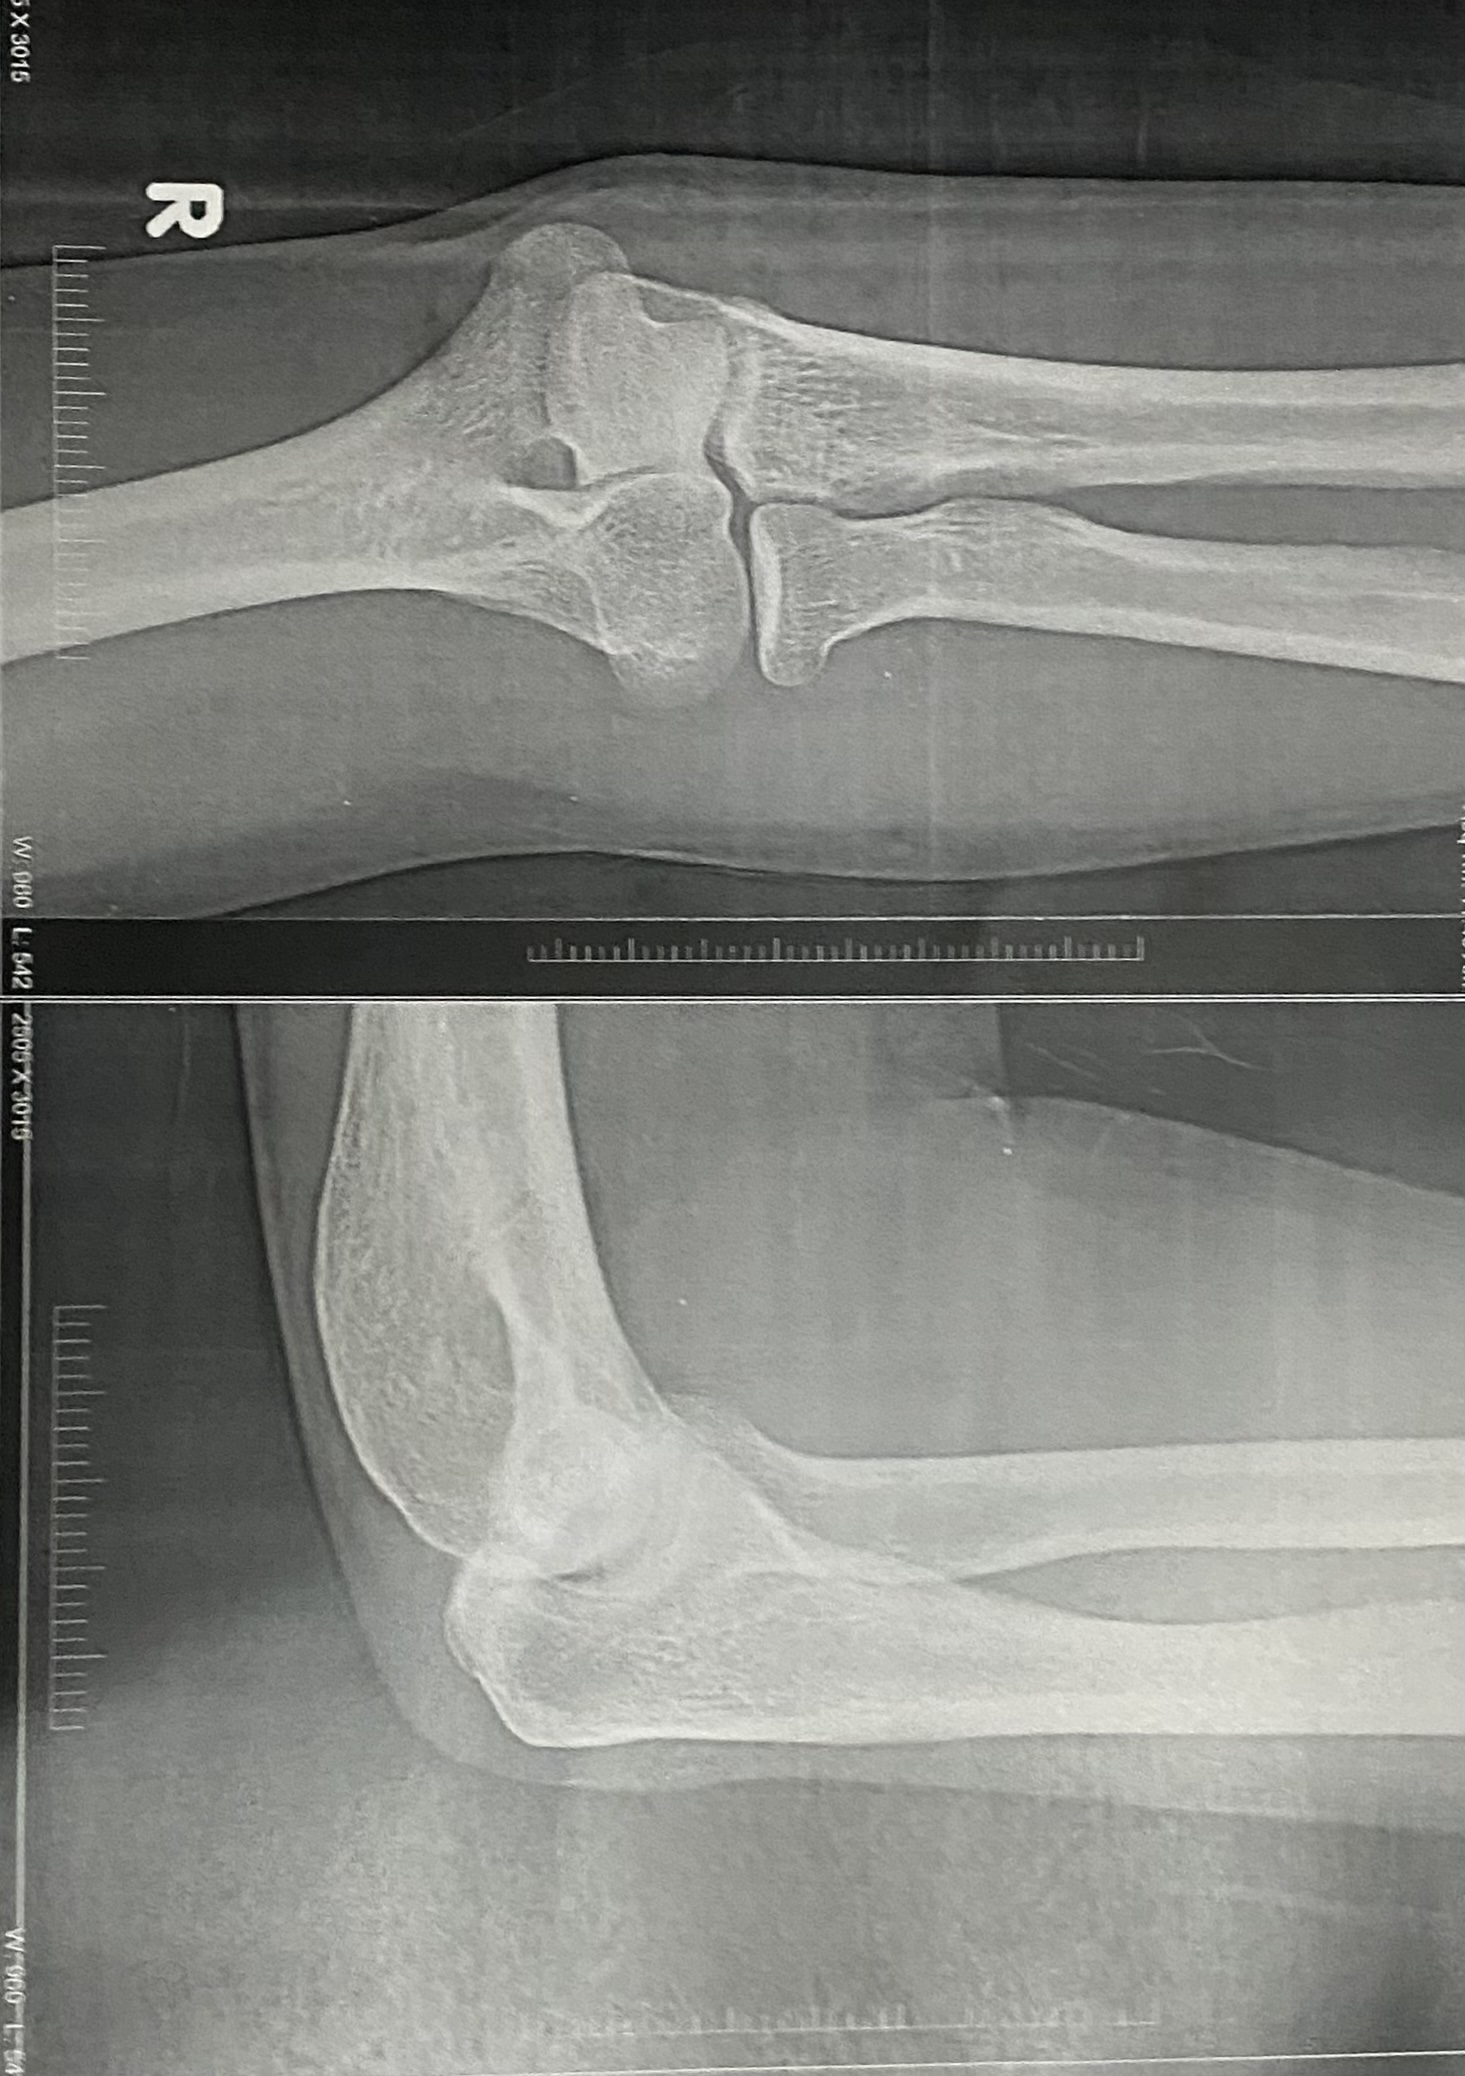

USG Right elbow-

Features of mild Right Olecranon bursitis